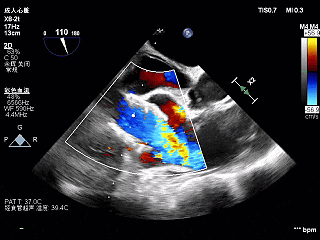

术前超声

超声所见:

主动脉瓣增厚,回声增强,右冠瓣舒张期脱向左室流出道,跨瓣血流线速度加快,峰值压差25mmHg,瓣口探及中重度偏心性反流,反流束冲击二尖瓣前叶及左室侧壁;二尖瓣口探及轻中度反流。

LVEF 46%(反流程度加重,可能导致高估)。

TEE短轴,无瓣周漏

TEE长轴,瓣膜深度可